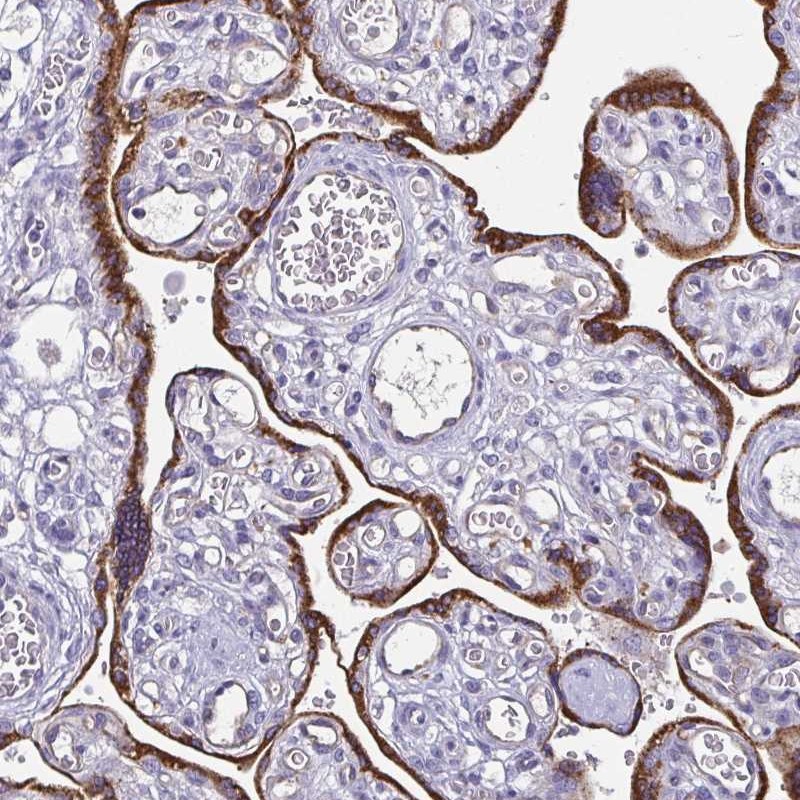

Immunohistochemical staining of human placenta shows strong cytoplasmic positivity in trophoblastic cells.